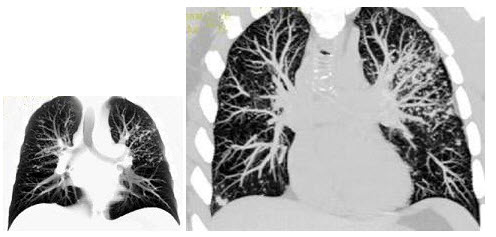

E.心脏搏动

18、单项选择题

患者腹痛,结合图像,最可能的诊断是()

A.淋巴瘤

B.幽门螺杆菌感染

C.胃炎

D.浸润性胃腺癌

E.以上都不是